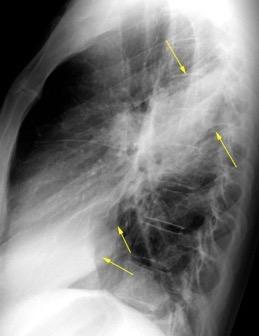

Marzo 2014: Perforación longitudinal distal secundaria a episodio de vómito (síndrome de Boerhaave). Derrame pleural izdo. que evoluciona a empiema.

Wang C-T et al. Tension hydropneumothorax in a Boerhaave syndrome patient: A case report . World J Emerg Med, 2021. Katabathina V et al. Nonvascular, nontraumatic mediastinal emergencies in adults:a comprehensive review of imaging findings. Radiographics. 2011.